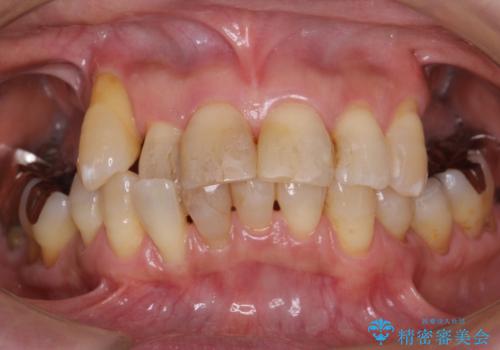

- 上の奥歯がないまま長年過ごしていたら前歯もぐらぐらしてきてしまったことを主訴に来院された患者様です。

奥歯の咬み合わせがないことにより前歯に負担がかかり動揺が出ていました。

精査したところ右下の奥歯も歯周病により保存不可能な状態でした。

なるべく予算を抑えたいとのご希望から、上顎は入れ歯、右下臼歯部はインプラントによる治療を行いました。

上の前歯は動揺を抑え、入れ歯の着脱にも耐えうるように被せ物を連結させることにしました。